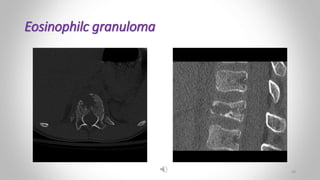

Eosinophilc granuloma :

• Is the mildest and most frequent form of langerhans cell histiocytosis .

• It occurs in children and young adults .

• Produces lytic lesions

• May be single or multiple.

• Most frequently in the skull, pelvis, femur and ribs.

• Extensive lesions may be seen giving rise to the so-called ‘geographic skull’.

• Long bone lesions show :

• Bone destruction which may be ill defined, having the features of an aggressive lesion

• Or well defined and may have a sclerotic rim.

• Periosteal reaction is sometimes seen .

 EG :

• ill-defined lucency within the femoral shaft with surrounding layering

periosteal reaction. 26